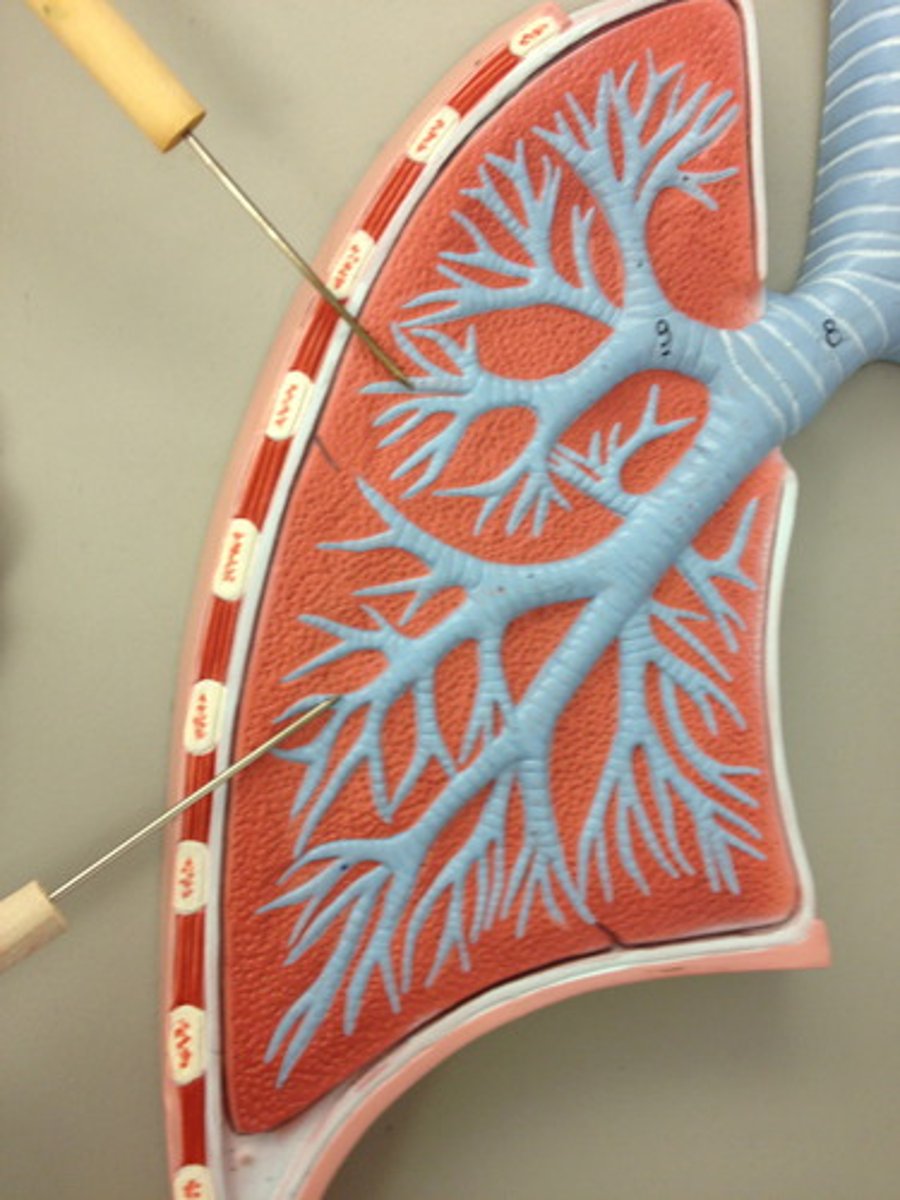

lung (normal)

alveolus (normal)

smoker's lung

alveolus (of smoker's lung)

carbon deposits (tar)

right lung

superior lobe of right lung

middle lobe of right lung

inferior lobe of right lung

right main bronchus

lobar bronchi

terminal bronchi

pleural sac

serous membrane that surrounds the lungs and has a visceral and parietal layer